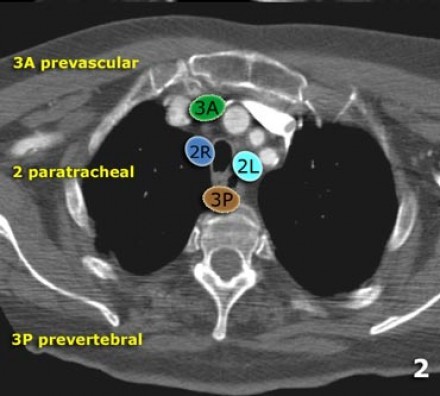

Linfonodo no estádio 2 em frente à traqueia (linfonodo 2R.)

Há também um pequeno linfonodo prevascular (linfonodo na estação 3A)

2R Linfonodos estendem-se para a borda lateral esquerda da traqueia.

Limite superior: borda superior do manubrio.

Limite inferior: intersecção da margem caudal da veia inominada (brachiocefálica esquerda) com a traqueia.

2L. Paratraqueal Superior Esquerda

Limite superior: borda superior do manúbrio

Limite inferior: borda superior do arco aórtico.